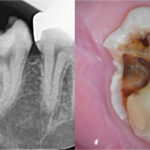

右下7番(第二大臼歯)の根の先に膿がたまっている根尖性歯周炎という状態でした。治療の選択肢として、現在入っているクラウンやメタルポスト(土台)を全て除去して、精密根管治療を行う方法が第一選択として挙げられます。しかし、今回は残存歯質量に不安がある点、古い修復物除去時に歯が割れる可能性がある点などから、通常の根管治療ではなく、意図的再植術の適応と診断しました。

③拡大視野での精査

色素で染め出しを行い、クラックの有無や、切断面の根管の形態(複根管やイスムスなど)を精査します。この工程は、裸眼で精査することは難しく、高倍率での顕微鏡下での精査が必要です。ここでもしもわずかなクラックが認められる場合、クラックが消失するまで根尖部分の切除を進めます。